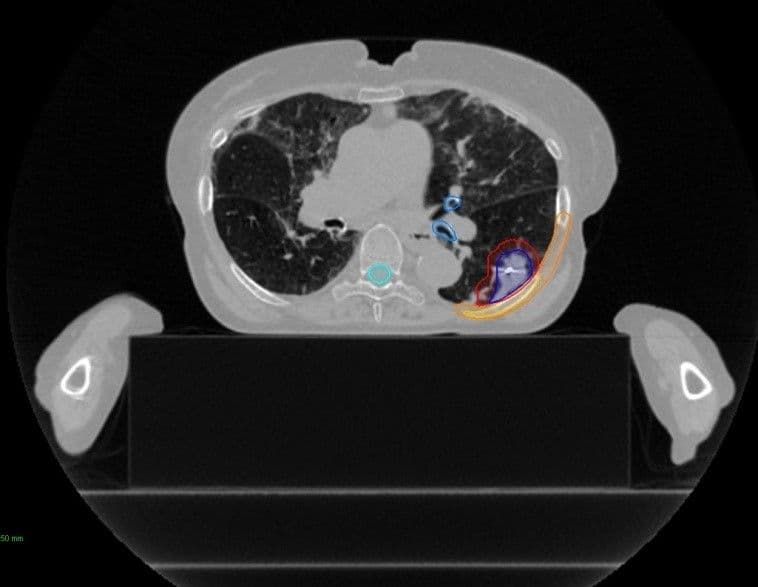

Because SRS delivers precisely targeted radiation at higher doses with tight tolerances spread across only a few treatment visits, it requires an increased level of attention to patient immobilization.

"As a long time CyberKnife user and a consulting physicist, I think its important to share solutions we’ve implemented with other centers to improve patient treatments and outcomes throughout the community. For the type of radiation therapy we deliver with the CyberKnife, we need a fast CT for a true breath hold without compromising the field of view, One of the most useful tools we have for set-up is what we call the ‘skinny pad’ from Orfit (Full Body Cushion). It’s only about 10cm thick and it’s very narrow, which enables the patient’s arms to rest below the back. This allows more of the patient’s outer torso diameter to be included in the beam entry angle."

The full body cushion allows the use of lateral fields to radiate the spine and posterior thorax, without the arms being located in the treatment field.